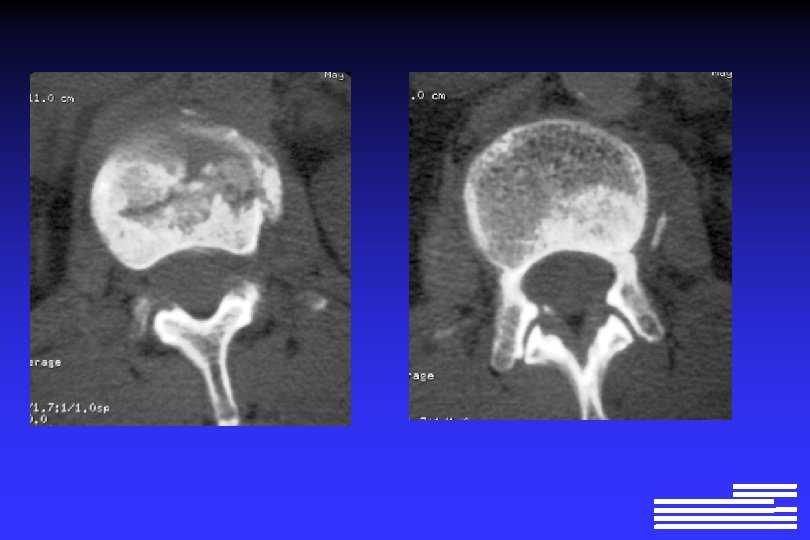

Explorations à effectuer pour le diagnostic positif et différentiel l Radiographie du squelette complet Ø Lésions lytiques à l’emporte-pièce Ø Lésions « ostéoporose diffuse » Ø Lésions condensantes (rares +++ !, 0, 5 à 3% des cas)